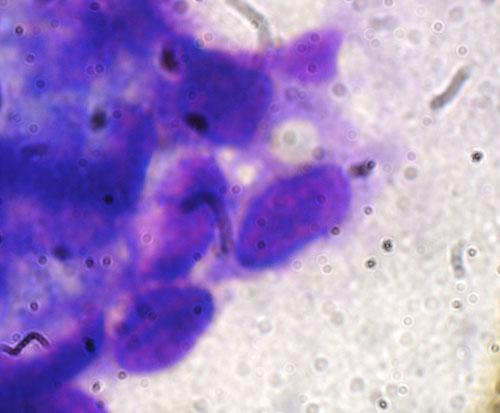

La cytologie par ponction de nodule montre des amas de cellules fusiformes à noyau oblong, à la chromatine finement piquetée, peu nucléolées, et à cytoplasme basophile (photo 4).

Photo 4 (*1000 immersion, RAL) : cytoponction d’un nodule, cellules fusiformes